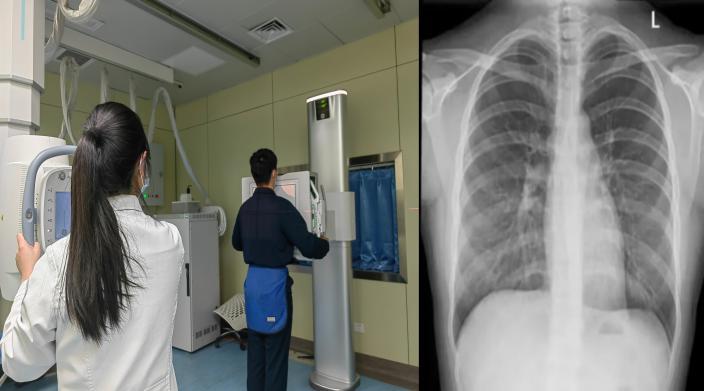

除了核磁共振,去医院检查时,我们接触更多的是X光和CT,这两项检查有辐射吗?

X光检查(胸片/骨片)的原理是快速给身体拍“黑白照片”,适用于骨折筛查、肺炎检查、脊柱侧弯评估等,辐射量约等于坐飞机往返北京和纽约(0.1mSv)。

资料图片

CT检查可以理解为360°分层扫描的“切片面包”,适用于脑出血、肿瘤筛查、肺结节、腹部病变以及其他复杂疾病的检查,辐射量约等于在自然环境中生活3年(2-15mSv)。

以常见的影像检查为例:拍一张X光片(胸片、四肢片)约2.0微西弗,相当于吃20根香蕉。做一次头部CT约200微西弗,相当于吃2000根香蕉。

对比一下你就放心了,一次常规医学检查的辐射远远达不到伤害人体的阈值!